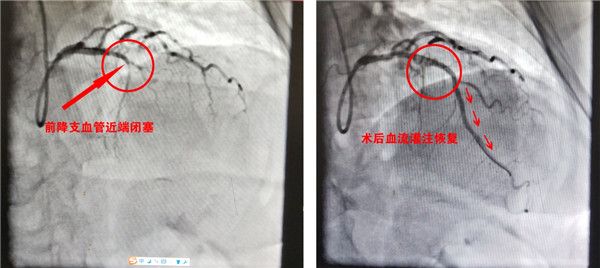

▲李先生术前术后冠脉造影对比

冠脉造影显示“前降支动脉近端完全闭塞”,立即球囊扩张、支架植入……李先生16时40分直达介入手术室,于17时25分开通闭塞血管。35分钟的“门球时间”(从入院到血管开通的时间),由于院前诊断明确、家属的果断,远远小于90分钟的国际标准,李先生术后恢复良好。